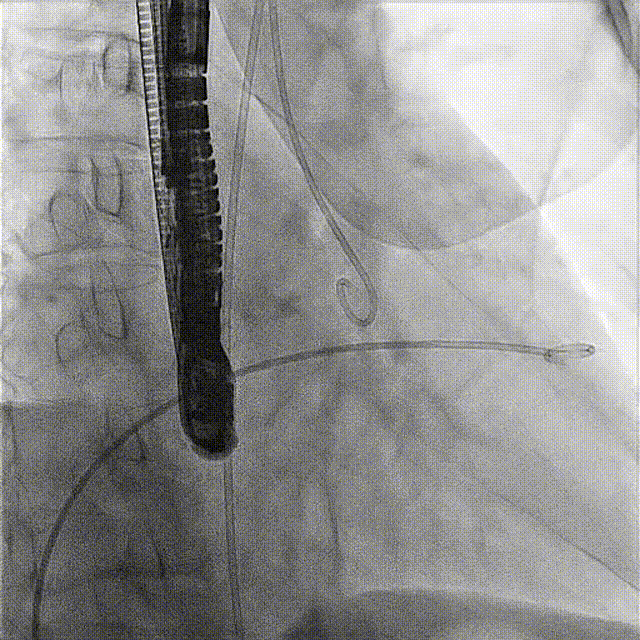

術(shù)前DSA

接受手術(shù)的為一名80歲男性,因“心悸2年,氣喘伴下肢水腫半年”入院。超聲心動(dòng)提示“極重度三尖瓣反流,右房及右室明顯擴(kuò)大,右心收縮功能輕度減低,左心收縮功能正常,肺動(dòng)脈壓力正常”。患者同時(shí)合并有“持續(xù)性房顫”及“慢性心力衰竭”,病史持續(xù)2年,規(guī)律口服抗凝及強(qiáng)心、利尿治療治療效果不佳,癥狀持續(xù)。經(jīng)廈心心臟團(tuán)隊(duì)評(píng)估后,認(rèn)為患者三尖瓣極重度反流并伴有心衰表現(xiàn),長(zhǎng)期內(nèi)科藥物治療效果不佳,且患者高齡、外科手術(shù)風(fēng)險(xiǎn)高,因此決定采用微創(chuàng)經(jīng)頸靜脈LuX-Valve Plus三尖瓣置換系統(tǒng)為患者治療。

術(shù)前經(jīng)過(guò)全面系統(tǒng)的評(píng)估后,考慮患者存在高齡、心功能減低、三尖瓣瓣環(huán)重度擴(kuò)張(三尖瓣極重度反流)等高危因素,因此廈心結(jié)構(gòu)心團(tuán)隊(duì)聯(lián)合超聲心動(dòng)、麻醉及護(hù)理團(tuán)隊(duì),制定了詳盡的圍術(shù)期治療方案及術(shù)中治療難點(diǎn)預(yù)案。術(shù)中,由王焱院長(zhǎng)主刀,在蘇茂龍主任超聲心動(dòng)團(tuán)隊(duì)的輔助,上海市第一人民醫(yī)院陸方林主任的協(xié)助下,僅用時(shí)30分鐘,即順利完成了三尖瓣原位置換的手術(shù)。術(shù)中患者血流動(dòng)力學(xué)穩(wěn)定,術(shù)后即刻顯示LuX-Valve Plus瓣膜位置良好,固定穩(wěn)定,瓣膜功能正常,無(wú)瓣周漏。